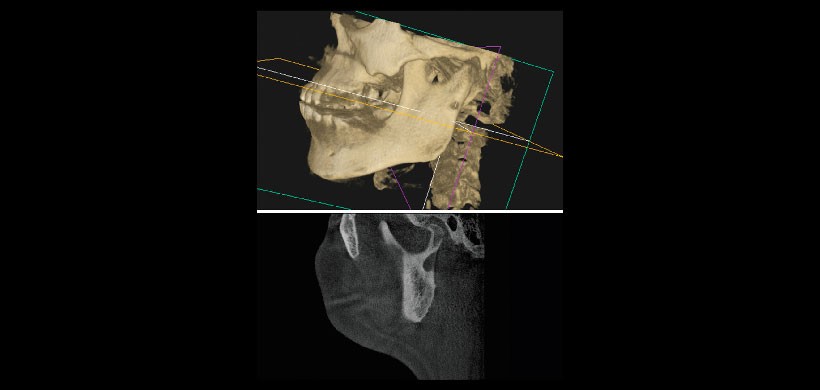

Fig 3. Tomografía computarizada de haz cónico. Reconstrucción en 3 dimensiones

de la mandíbula y el maxilar superior muestra la depresión lingual a través de la cara vestibular adelgazado o perforada de la rama mandibular izquierdo. Corte sagital del lado izquierdo muestra los detalles de la concavidad (parte inferior).